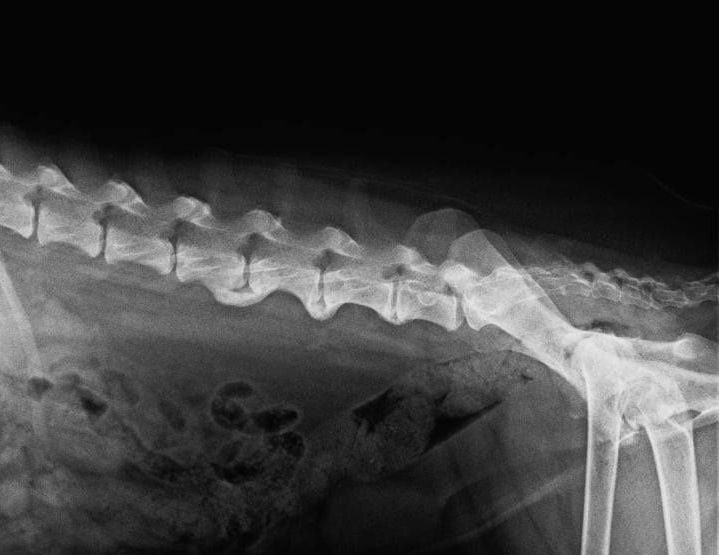

Gerade wenn Muskulatur auftrainiert werden soll ohne dabei erkrankte Gelenke unnötig zu belasten, kann man mit dem Unterwasserlaufband für Hunde einfach wahnsinnig gute Erfolge erzielen. Dies ist zum Beispiel der Fall bei an HD erkrankten Hunden, nach Operationen des Bewegungsapparats, wie zum Beispiel nach einem Kreuzbandriss, aber auch bei neurologischen Erkrankungen, wie zum Beispiel dem Bandscheibenvorfall, diese Therapieform ist für den Hund hervorragend geeignet, um Bewegung wieder zu erlangen.

Für eine Studie aus dem Jahre 2018 wurden Labrador Retriever mit und ohne Ellenbogendysplasie einer kinematischen Analyse unterzogen, um die Auswirkungen einer einzelnen Hydrotherapie-Sitzung auf den Bewegungsumfang, die Schrittlänge und die Schrittfrequenz zu untersuchen.

Der Bewegungsumfang war bei den gesunden Hunden bei Studienbeginn größer als bei den erkrankten Hunden, die Hydrotherapie vergrößerte aber den Bewegungsumfang der Vordergliedmaßen beider Gruppen - und Hunde mit Ellbogendysplasie zeigten eine größere Verbesserung des Bewegungsumfangs als gesunde Hunde.